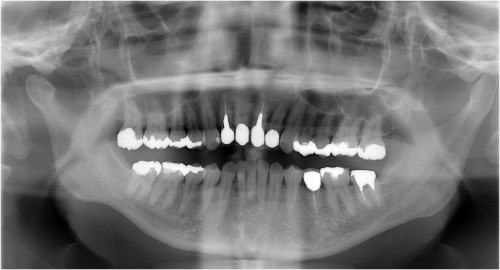

術前

被せ物の二次虫歯と根の破折

抜歯後

抜歯後2ケ月後経過

抜歯後4ケ月半後経過

インプラント埋入

ピエゾサージェリー

インプラント埋入後

オペ時のISQ値

土台装着

被せ物装着

術後